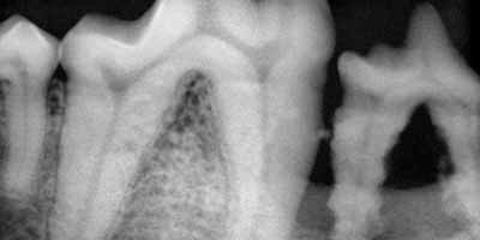

• Feb 20 Periodontal Disease - Evaluation and Treatment of a Hidden Disease

Why Is Periodontal Disease So Common, Yet So Often Overlooked And Under Treated? One reason may be that many owners do not ...

• Feb 10 Dental Health and Periodontal Disease

February is National Pet Dental Health Month! However, we must not forget that oral health is a concern for all pets, all year ...